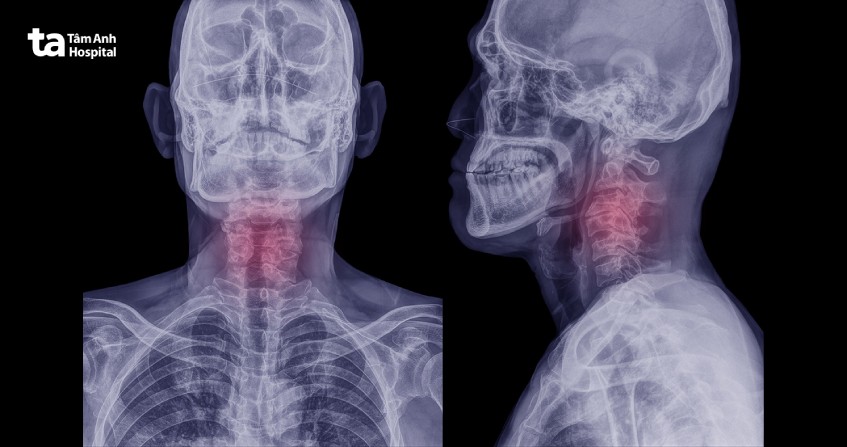

Chụp X quang cột sống cổ giúp tạo nên hình ảnh giải phẫu 7 đốt sống đầu tiên của cột sống. Hình ảnh X quang cột sống cổ giúp bác sĩ đưa ra chẩn đoán về những chấn thương hoặc bệnh lý tại cột sống cổ.

Chụp X quang cột sống cổ là kỹ thuật chẩn đoán hình ảnh quen thuộc có thể giúp bác sĩ phát hiện các triệu chứng lâm sàng của những bệnh lý hoặc tổn thương tại vùng cột sống cổ. Kỹ thuật chụp X-quang cột sống cổ sử dụng các chùm tia bức xạ X được phát từ thiết bị X-quang chiếu qua vùng cổ để tạo nên hình ảnh cấu trúc rõ nét của đốt sống cổ. Những vùng có cấu trúc dày đặc như xương sẽ hấp thụ ít tia X nên trên phim X-quang sẽ có màu trắng, trong khi đó các mô mềm như da, mạch máu, mỡ hấp thụ nhiều tia bức xạ hơn nên sẽ có màu xám đen trên phim X-quang.

Kỹ thuật X quang cột sống cổ sẽ chụp tổng cộng 7 đốt sống cổ (7 đốt sống đầu tiên của cột sống). Ảnh phim X-quang cột sống cổ sẽ giúp bác sĩ quan sát cấu trúc các đốt sống cổ và mô mềm xung quanh khu vực này.

Chụp X quang cột sống cổ giúp phát hiện sớm tổn thương, thoái hóa hoặc sai lệch cấu trúc, từ đó hỗ trợ bác sĩ đưa ra phác đồ điều trị chính xác. Tại Bệnh viện Đa khoa Tâm Anh, quy trình chụp được thực hiện với thiết bị hiện đại, cho hình ảnh rõ nét, giảm thiểu phơi nhiễm tia X và đảm bảo an toàn cho người bệnh.